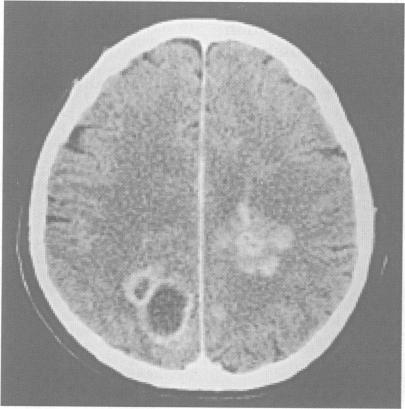

One hundred patients affected by multifocal brain lesions were investigated by serial stereotactic biopsy. Systemic diseases and primary neoplasms elsewhere were previously ruled out. The histological diagnosis obtained in this series comprises malignant gliomas in 37% of patients; primary non-Hodgkin's brain lymphoma in 15%; metastatic brain tumours in 15% (no evidence of the primary tumour at the time of stereotactic surgery); low grade gliomas in 12%; infective diseases in 10% (including brain abscesses and multifocal viral encephalitis); and ischaemic lesions in 6%. In addition, two patients with germinomas, two with primitive neuroepithelial tumours, two with multiple telangiectases, and one with a teratoma were also included in this series. Histological findings obtained by stereotactic procedures guided the choice of treatment, avoiding the risks of blind treatments. Indications and future perspectives for stereotactic surgery in multifocal brain lesions are discussed with emphasis on advances in diagnostic and therapeutic tools.

通过系列立体定向活检对100例患有多灶性脑病变的患者进行了研究。此前已排除全身性疾病和其他部位的原发性肿瘤。该系列病例的组织学诊断包括:37%的患者为恶性胶质瘤;15%为原发性非霍奇金脑淋巴瘤;15%为脑转移瘤(立体定向手术时未发现原发性肿瘤证据);12%为低级别胶质瘤;10%为感染性疾病(包括脑脓肿和多灶性病毒性脑炎);6%为缺血性病变。此外,该系列还包括2例生殖细胞瘤、2例原始神经上皮肿瘤、2例多发性毛细血管扩张症和1例畸胎瘤患者。立体定向手术获得的组织学结果指导了治疗方案的选择,避免了盲目治疗的风险。本文讨论了多灶性脑病变立体定向手术的适应证和未来前景,重点介绍了诊断和治疗工具的进展。